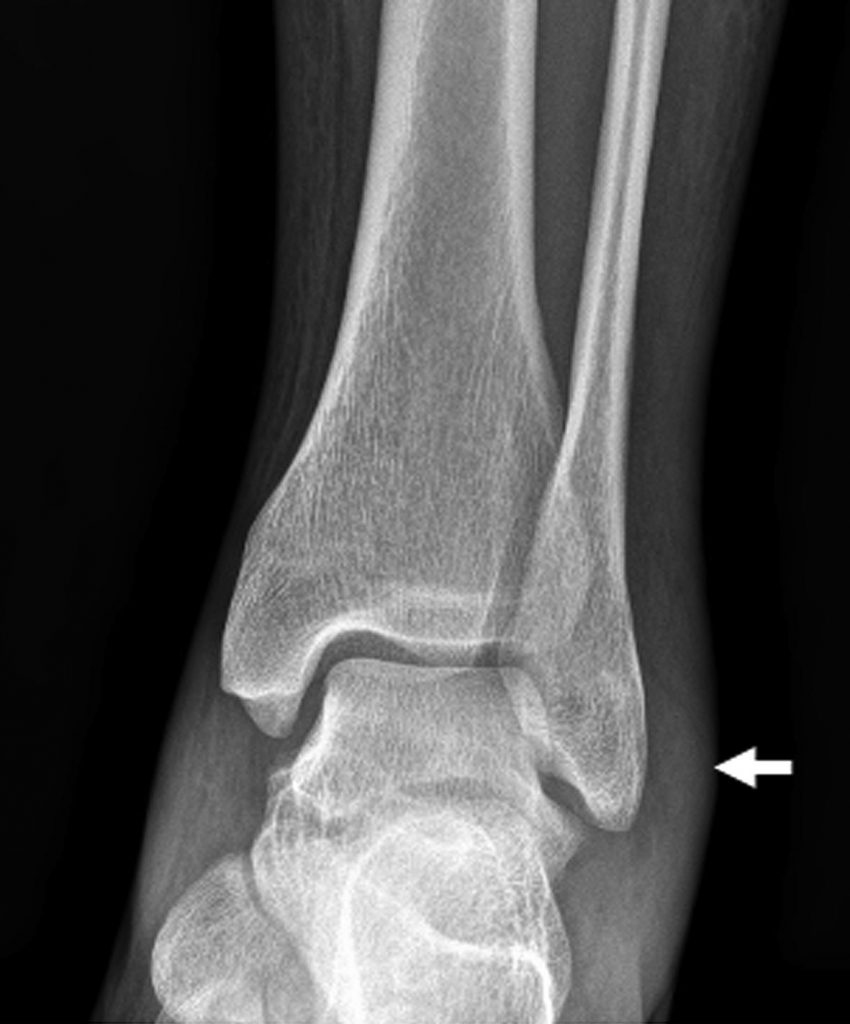

En cas d’entorse simple (lésion ligamentaire pure), les radiographies sont normales ou peuvent montrer un épaississement des parties molles en regard du ligament atteint (figures 79.3). Une avulsion osseuse de l’enthèse ligamentaire sur le site d’insertion du ligament peut être visible (figure 79.4).

Fig. 79.3 Entorse de cheville.

Radiographie de cheville de face montrant un épaississement des parties molles en regard de la malléole latérale due à l’œdème post-traumatique (flèches) et confirmant l’absence de lésions osseuses.

Source : CERF, CNEBMN, 2022.